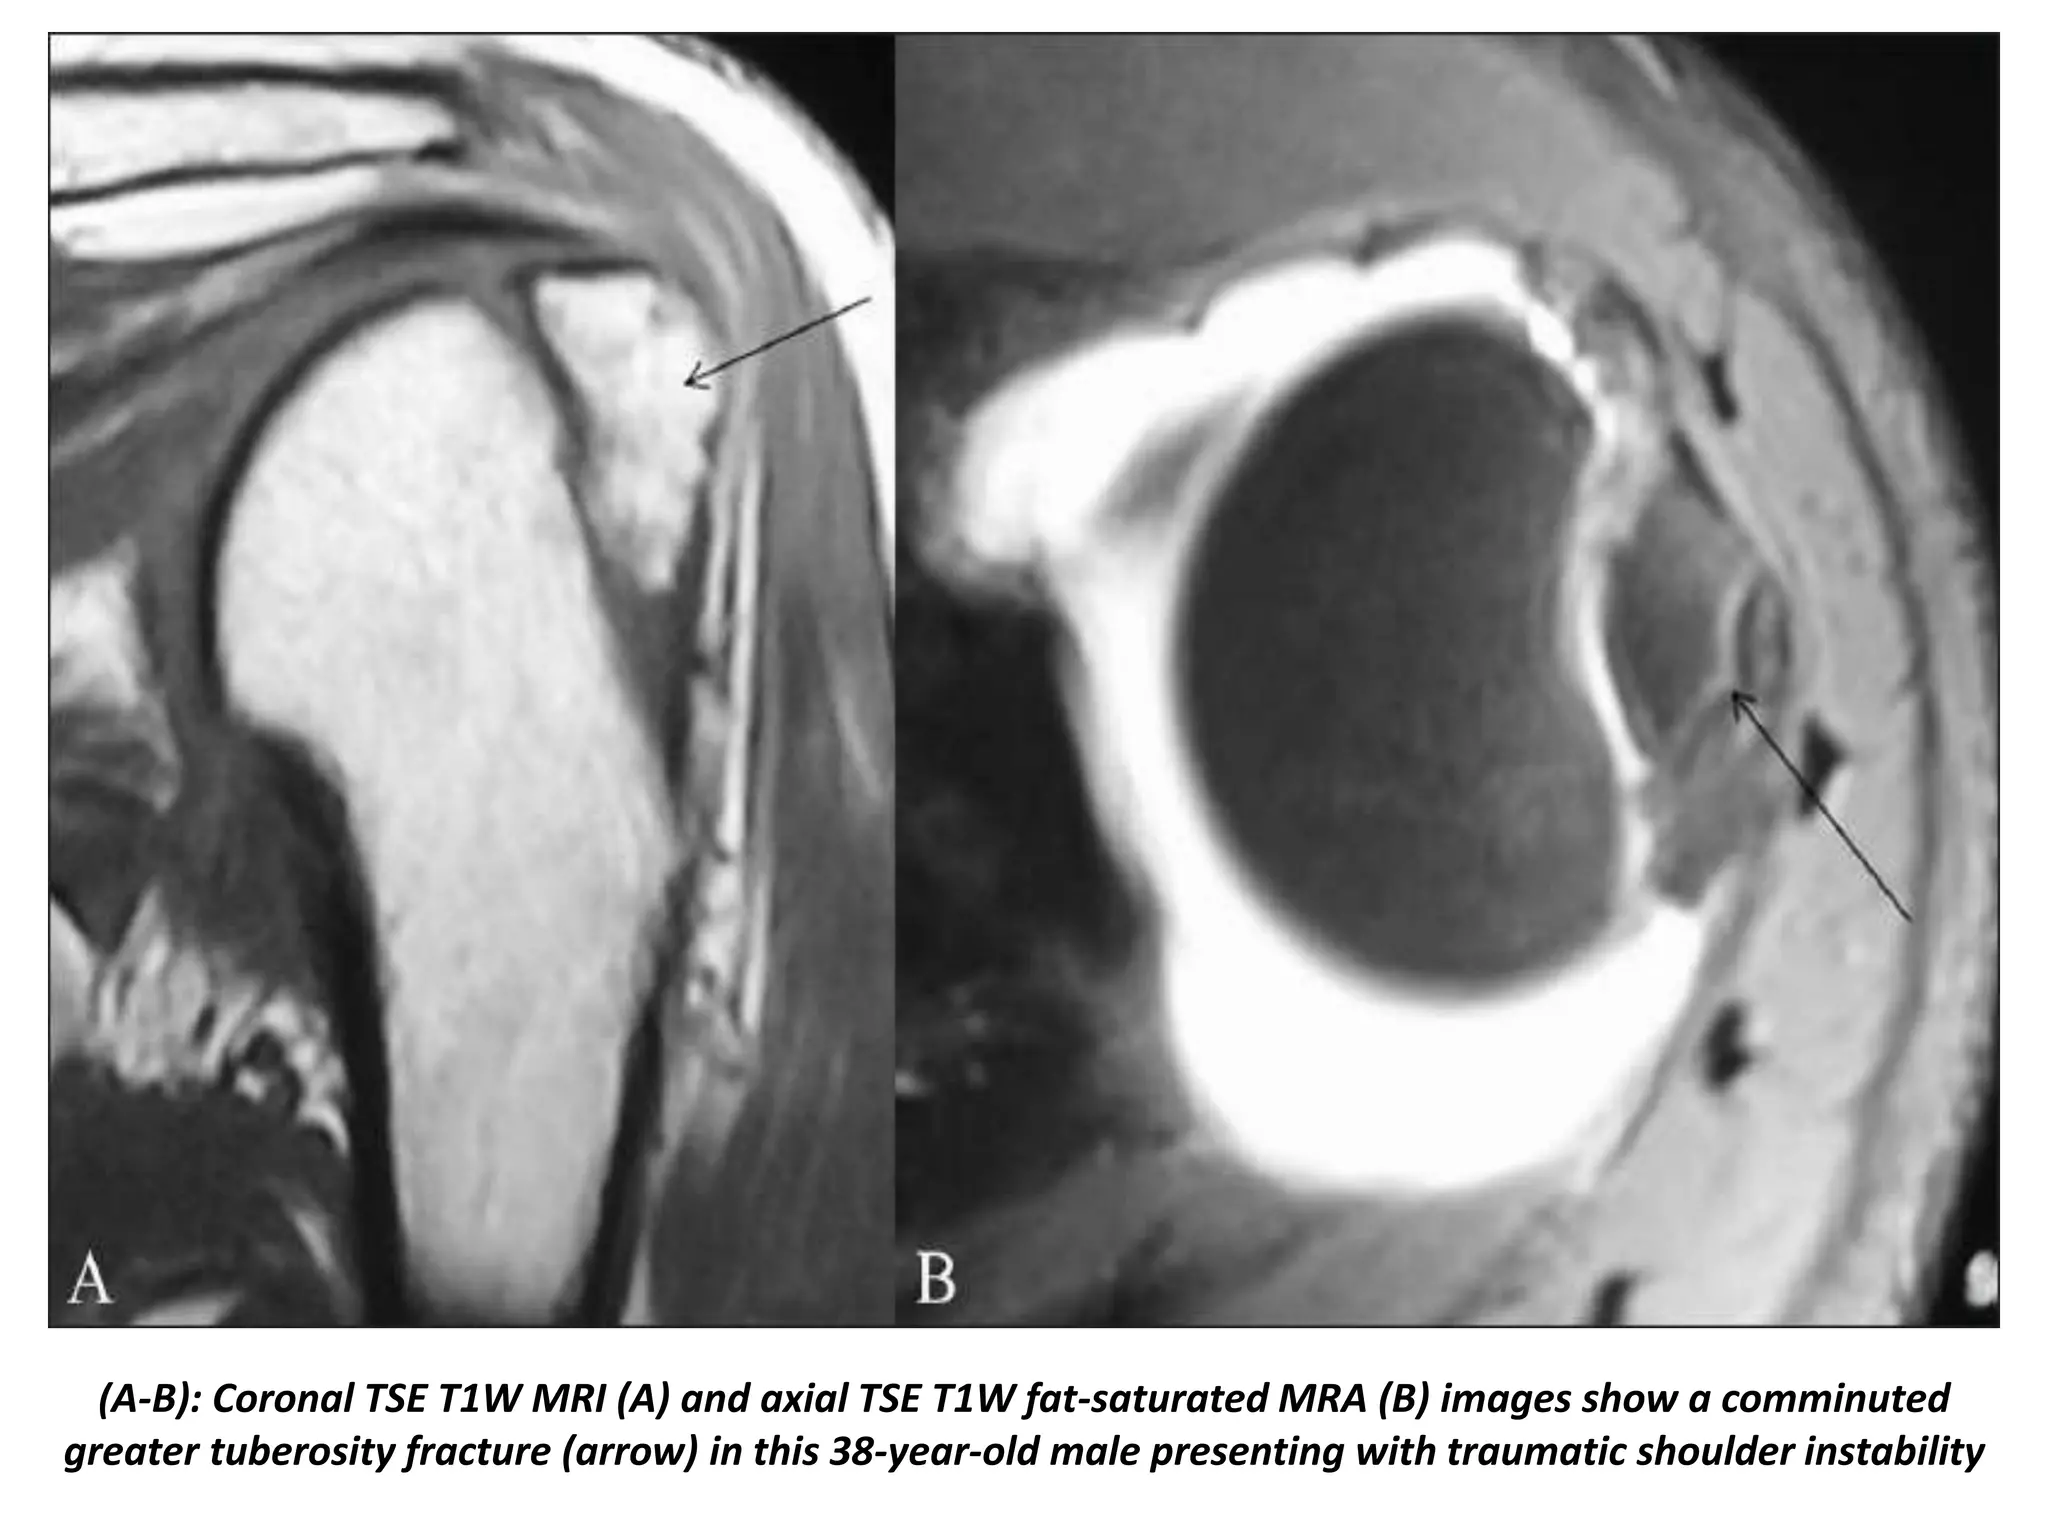

From radnucleus.wordpress.com

History of shoulder dislocation Radnucleus Icd 10 For History Of Shoulder Dislocation  The code is valid during the current fiscal year for the. Dislocations are joint injuries that force the ends of your bones out of position. The cause is often a fall or a blow (for instance,. Icd 10 code for unspecified dislocation of right shoulder joint, initial encounter. Z87.828 is a billable diagnosis code used to specify a medical diagnosis. Icd 10 For History Of Shoulder Dislocation.